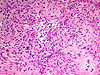

CASO N° 3 (Dr. Abel e Dr. Delgado)

Paciente do gênero masculino, 21 anos de idade, apresenta uma lesão no palato duro.